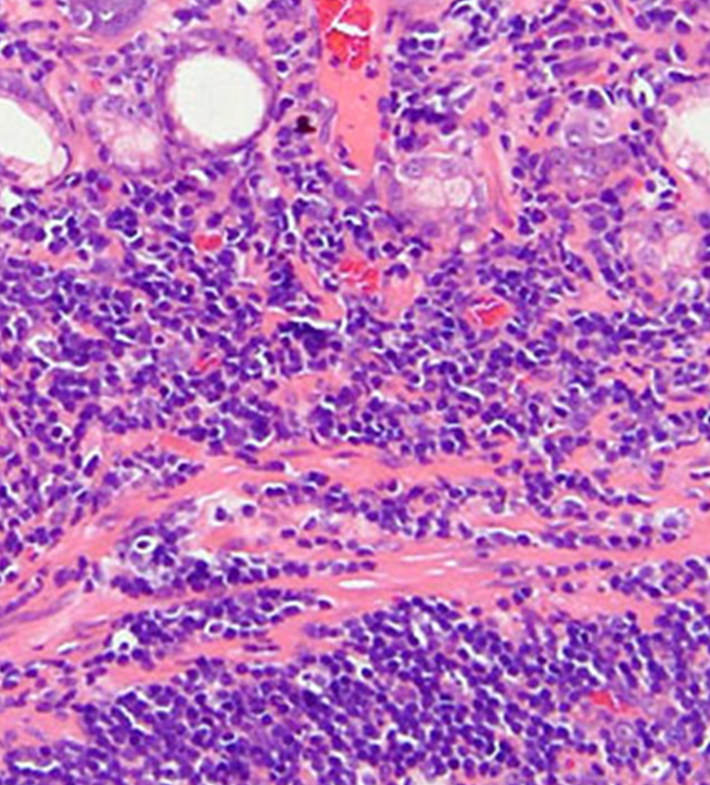

好酸球性胃腸炎 (Eosinophilic Gastroenteritis, EGE): LPEと比較して稀な形態ですが、一般に重度な臨床経過を辿ることが知られています 。組織学的に中等度から多数の好酸球が胃腸管壁に浸潤している場合に、「好酸球性胃腸炎」という診断名が与えられます。特にEGEは若齢の雄で多く見られるという疫学的報告があり 、臨床徴候には、慢性または間欠性の下痢(粘液や新鮮血を伴うこともある)、嘔吐(重症例では噴出性のこともある)、体重減少、食欲不振、および元気消失などが含まれます 。身体検査では、腸管ループの触知可能な肥厚や、腹腔内リンパ節の腫大が認められることがあります 。病理学的な所見として、EGEにおける好酸球の浸潤は、粘膜層に限定されず、粘膜下層、筋層、さらには漿膜に至るまで、腸管壁の深部構造全体に及ぶことが顕微鏡画像で示されています 。このような広範囲にわたる浸潤が、重度の嘔吐や腸管の肥厚といった臨床症状の原因となります〔Hoefer et al.2014〕。